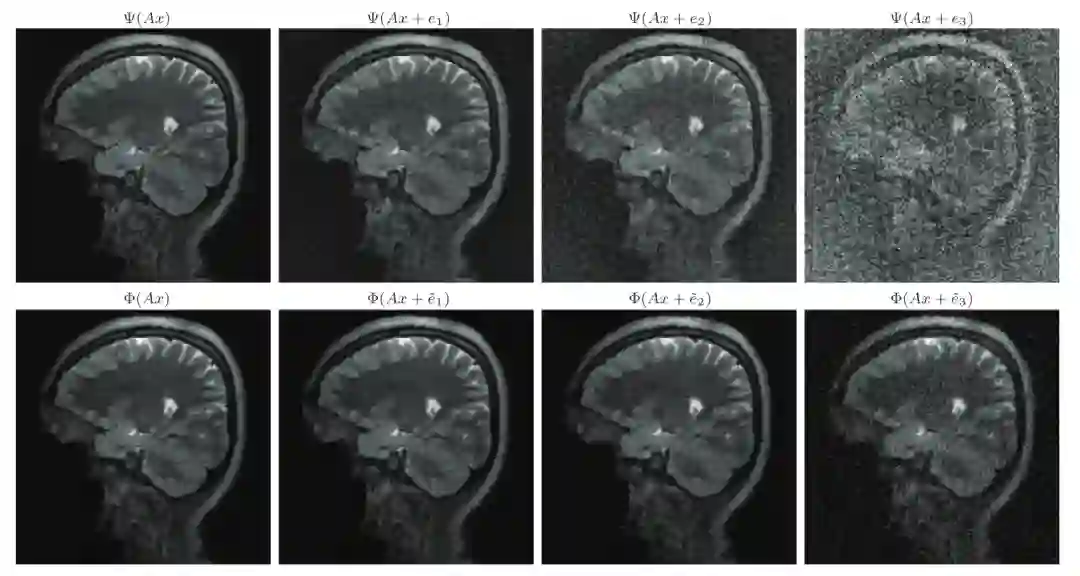

FIRENETs对扰动具有鲁棒性

在稳定性测试中,团队将 FIRENETs 与V. Antun等人(2020)开发的AUTOMAP网络进行对比。如下图中的上行所示,AUTOMAP网络重建很不稳定,导致图像完全变形。下行则是使用FIRENETs网络的重建结果。即使在最差的重建结果中,它仍然保持稳定。

这证明了由FIRENETs算法所计算的神经网络在小波中稀疏的图像中,在对抗扰动方面具有稳定性,而且同时能够维持一定的准确性。